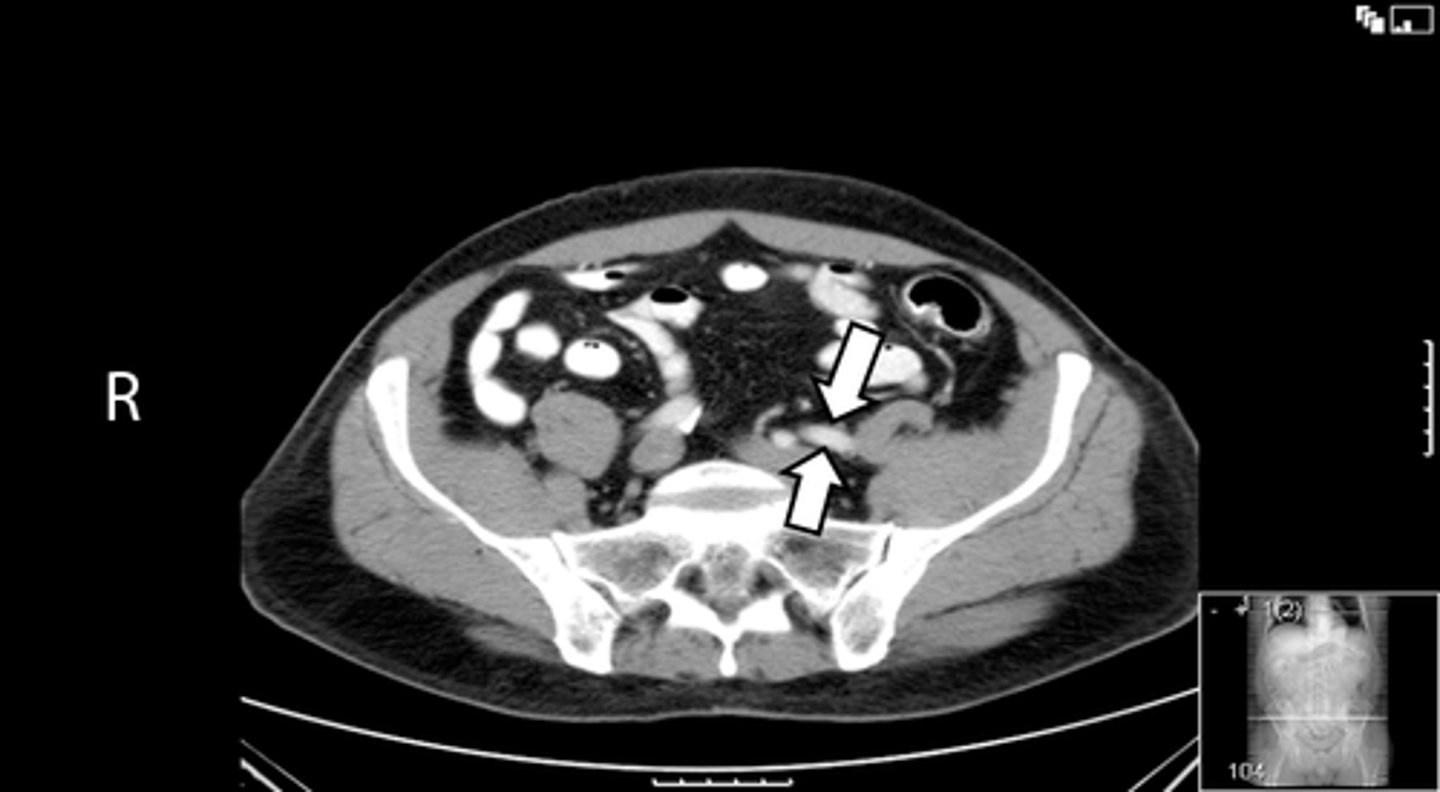

Axial male pelvis CT

What is the image?

<p>What is the image?</p>